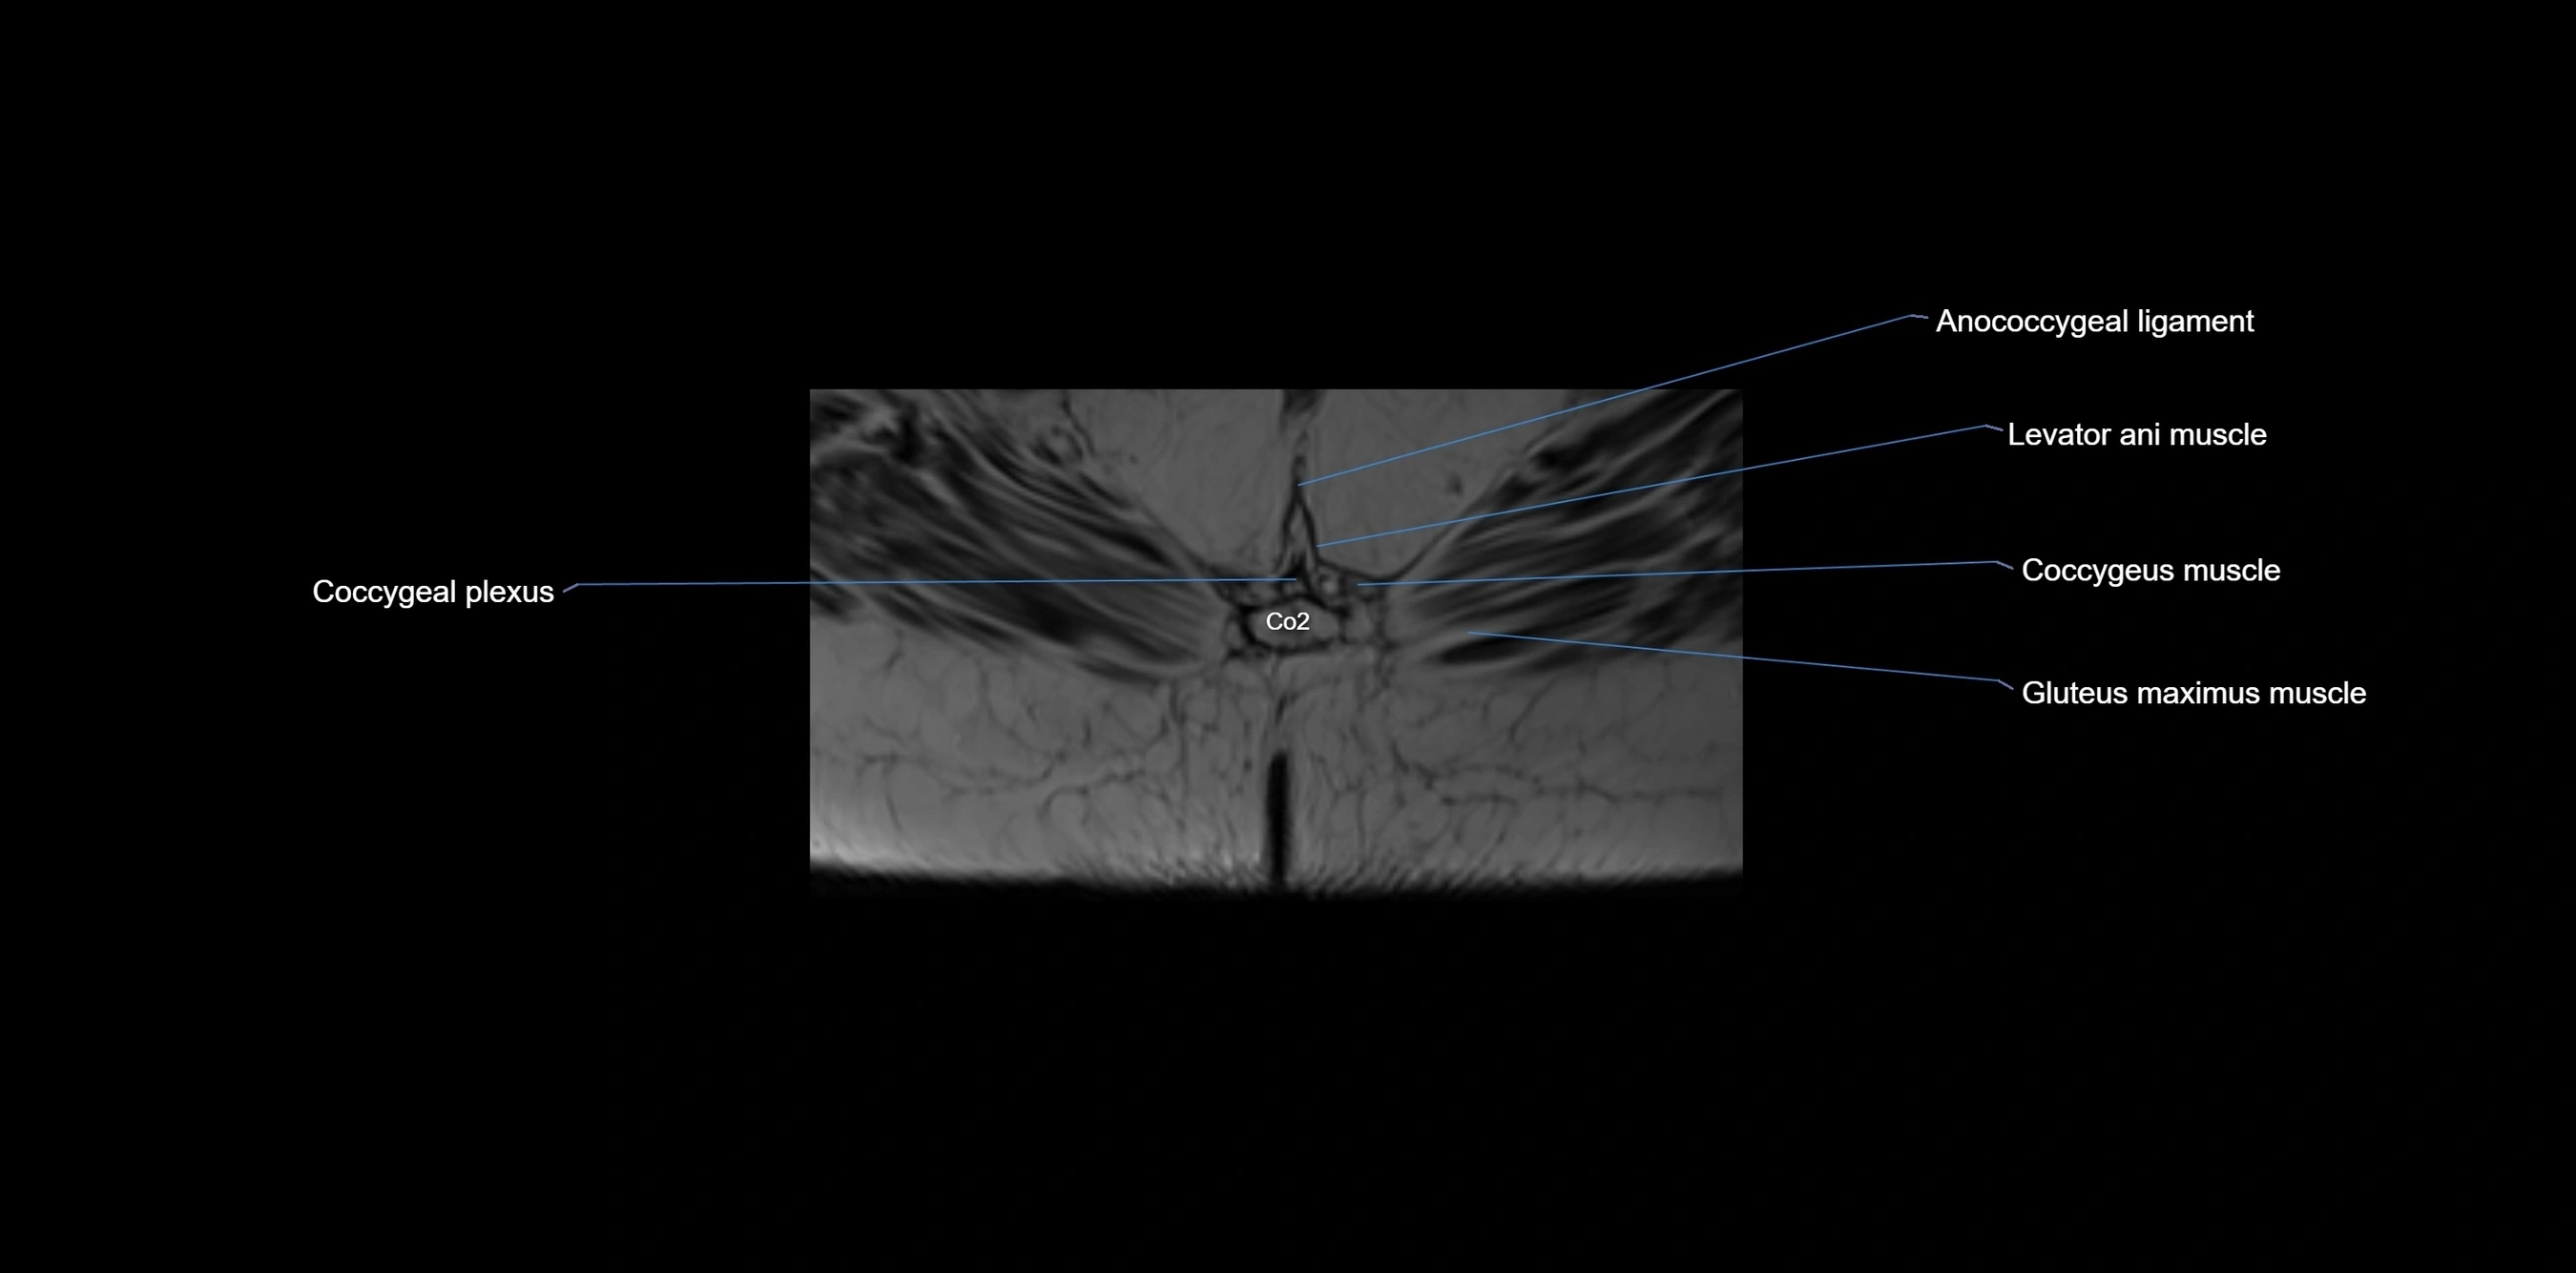

MRI image

image